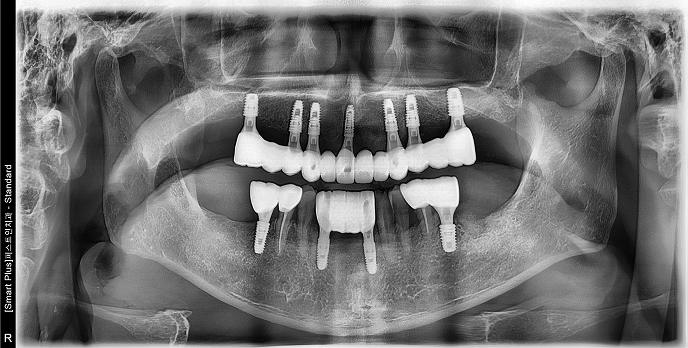

• 70대 남성 | 치주염 | 임플란트 | 치료기간 4개월

Before 2024.12.06

After 2025.04.11

• 80대 여성 | 틀니불편 | 임플란트, 상악동거상술 | 치료기간 7개월

Before 2024.08.06

After 2025.03.20